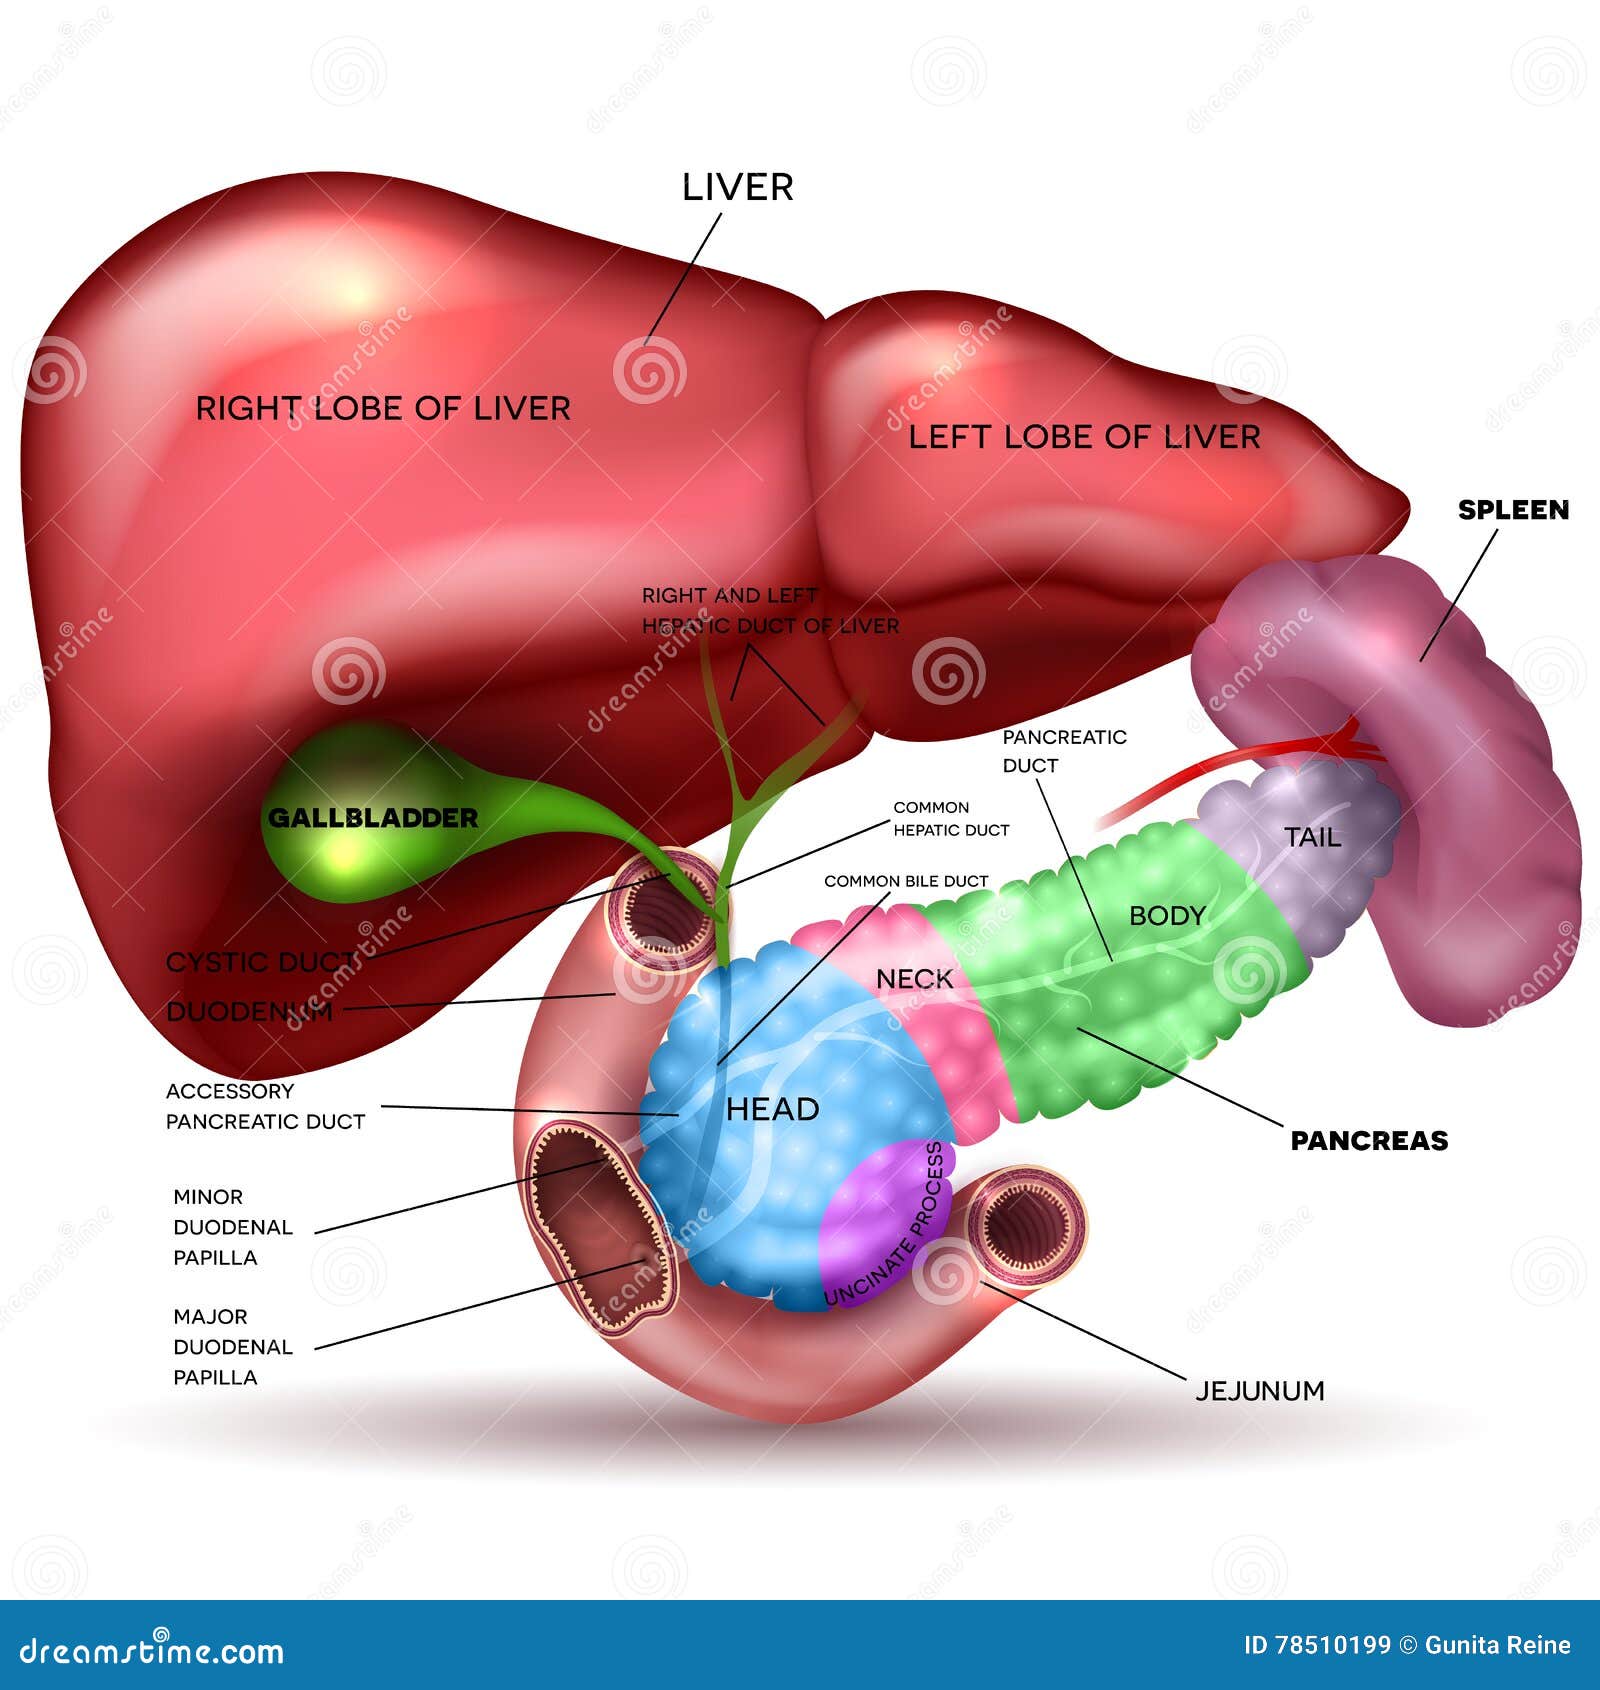

Leber, Pankreas, Gallenblase Vektor Abbildung Illustration von verdauungsfördernd, anal 78510199

De galblaas. Anatomie van de galblaas en galwegen. Anatomie van de twaalfvingerige darm en de

Anatomy of the gallbladder and bile ducts Surgery Oxford International Edition

Lever (Hepar)Galwegen en Galblaas